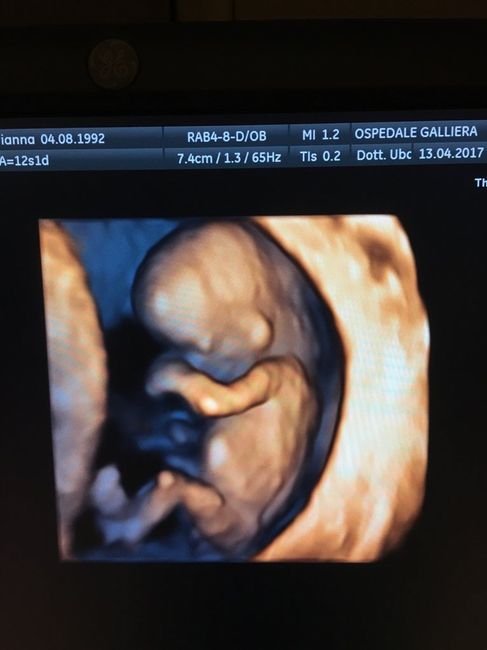

Secondo il ginecologo è una femminuccia

È stata per me L ecografie più emozionante di tutte, vederlo tutto formato e saltare da una parte all altra è qualcosa di indescrivibile, vi allego le fotine